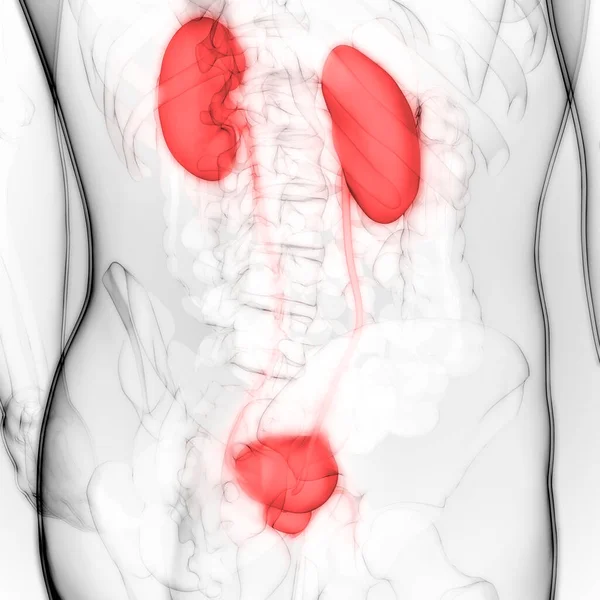

İdrar torbası anatomisi olan erkek idrar sistemi böbrekleri. 3d

ArkaplanGrafikselresimlemedizaynİzole edilmişkişiİnsaninsanlarSoyutSağlıksağlıklıİlaçerkekTıbbifasulyesiluetPankartgövdeHastalıkİçeridebiyolojiBilimkanserSistemAcıorgKasİskeletanatomiKas gücüx ışınıfizyolojiBöbrekTümöranatomikİdrar torbasıÜreterİdrarProstatÜretraÜrolojibilgi grafiği3B illüstrasyonnefronProstat bezinefrolojiBenzer İçerikler